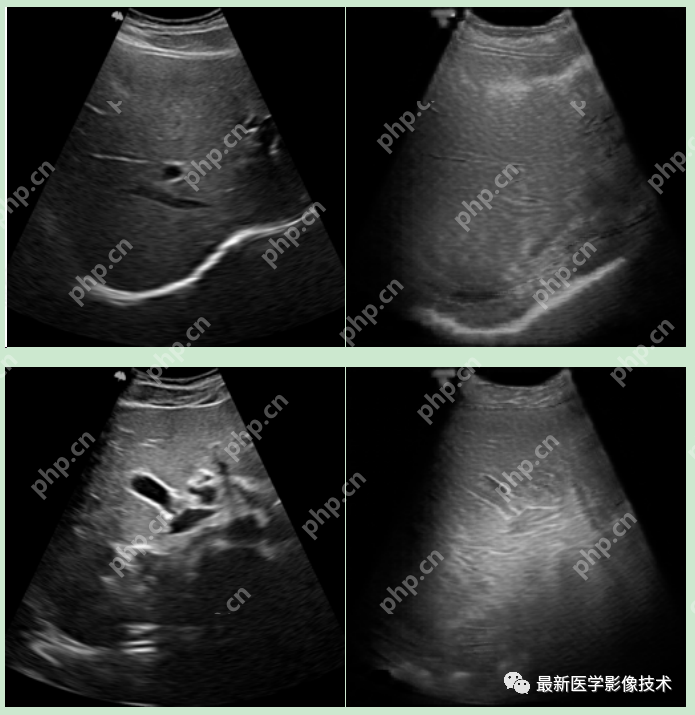

6、测试集部分生成结果

左图为低质量图像,右图为生成的高质量图像。